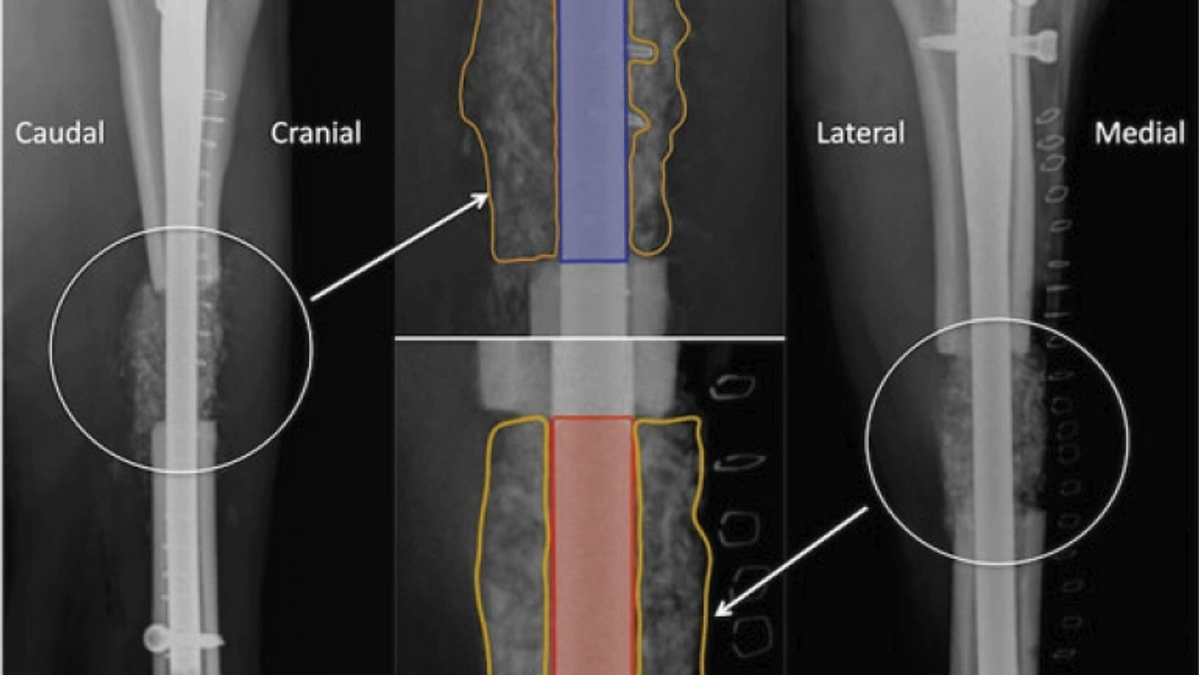

The formulation of appropriate postoperative strategies, following fracture repair, currently involves an understanding of radiological and clinical outcome measures. This study has evaluated several modalities used to assess the progression of bone healing in a sheep tibial segmental defect model. Measures of defect optical density and volumetric data including bone density (BD), bone volume (BV) and bone mass (BM) were compared with qualitative data involving visual appraisal of radiographs [% bridging callus and modified radiographic union score tibia (mRUST)] and a clinical outcome measure (locomotory function). Percent bridging callus and mRUST measures displayed strong correlation (r = 0.999), while locomotory function was weakly correlated with bridging callus (r = 0.029) and mRUST (r = 0.046). There was moderate to strong correlation between the qualitative and quantitative data. Bone density, BV and BM showed strong correlations within this dataset (BD-BV, r = 0.814; BD-BM, r = 0.818; BV-BM, r = 1.000). Likewise, optical density measures were strongly correlated with BD (r = 0.824), BV (r = 0.957) and BM (r = 0.959). The utilization of both qualitative and quantitative data, in assessment of the progression of fracture healing, has provided valuable insight. Measures of optical density have been shown to make a substantial contribution to this assessment and which should be considered for use in studies evaluating fracture healing.

This article was featured on the cover of the journal (January, 2018)